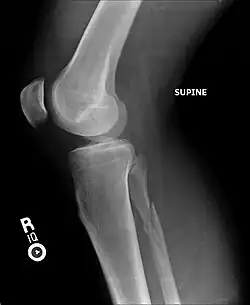

Ankle radiographs are used to detect widening of the tibiofibular syndesmosis or medial clear space. The medial clear space is the area between the talus of the ankle and the medial malleolus. Damage to the deltoid ligament and syndesmotic ligaments result in mortise instability, causing the talus to laterally shift and widen the medial clear space.[4][12] A clinical study, conducted in 2006 and published in the Journal of Bone and Joint Surgery, found that the medial clear space size of a normal ankle and an injured ankle measured at 4 millimetres and 5.4 millimetres in length respectively.[11] To confirm diagnosis, full-leg radiographs are used to inspect for fractures of the proximal fibula and widening of the interosseous clear space (or tibiofibular clear space). The interosseous clear space is the area between the medial side of the fibula and lateral side of the tibia. A peer-reviewed study, published in Injury in 2004, found that an interosseous clear space greater than 10 millimetres indicates diastasis of the syndesmotic ligaments.[4]

X-ray, CT, or MRI scans can be used to diagnose the extent of the Maisonneuve fracture's damage and determine whether it is a simple or comminution fracture.[8] During diagnosis, a supination-external rotation pattern of injury may also be concluded if there is an isolated fracture of the posterior tubercle of the tibia.[9]